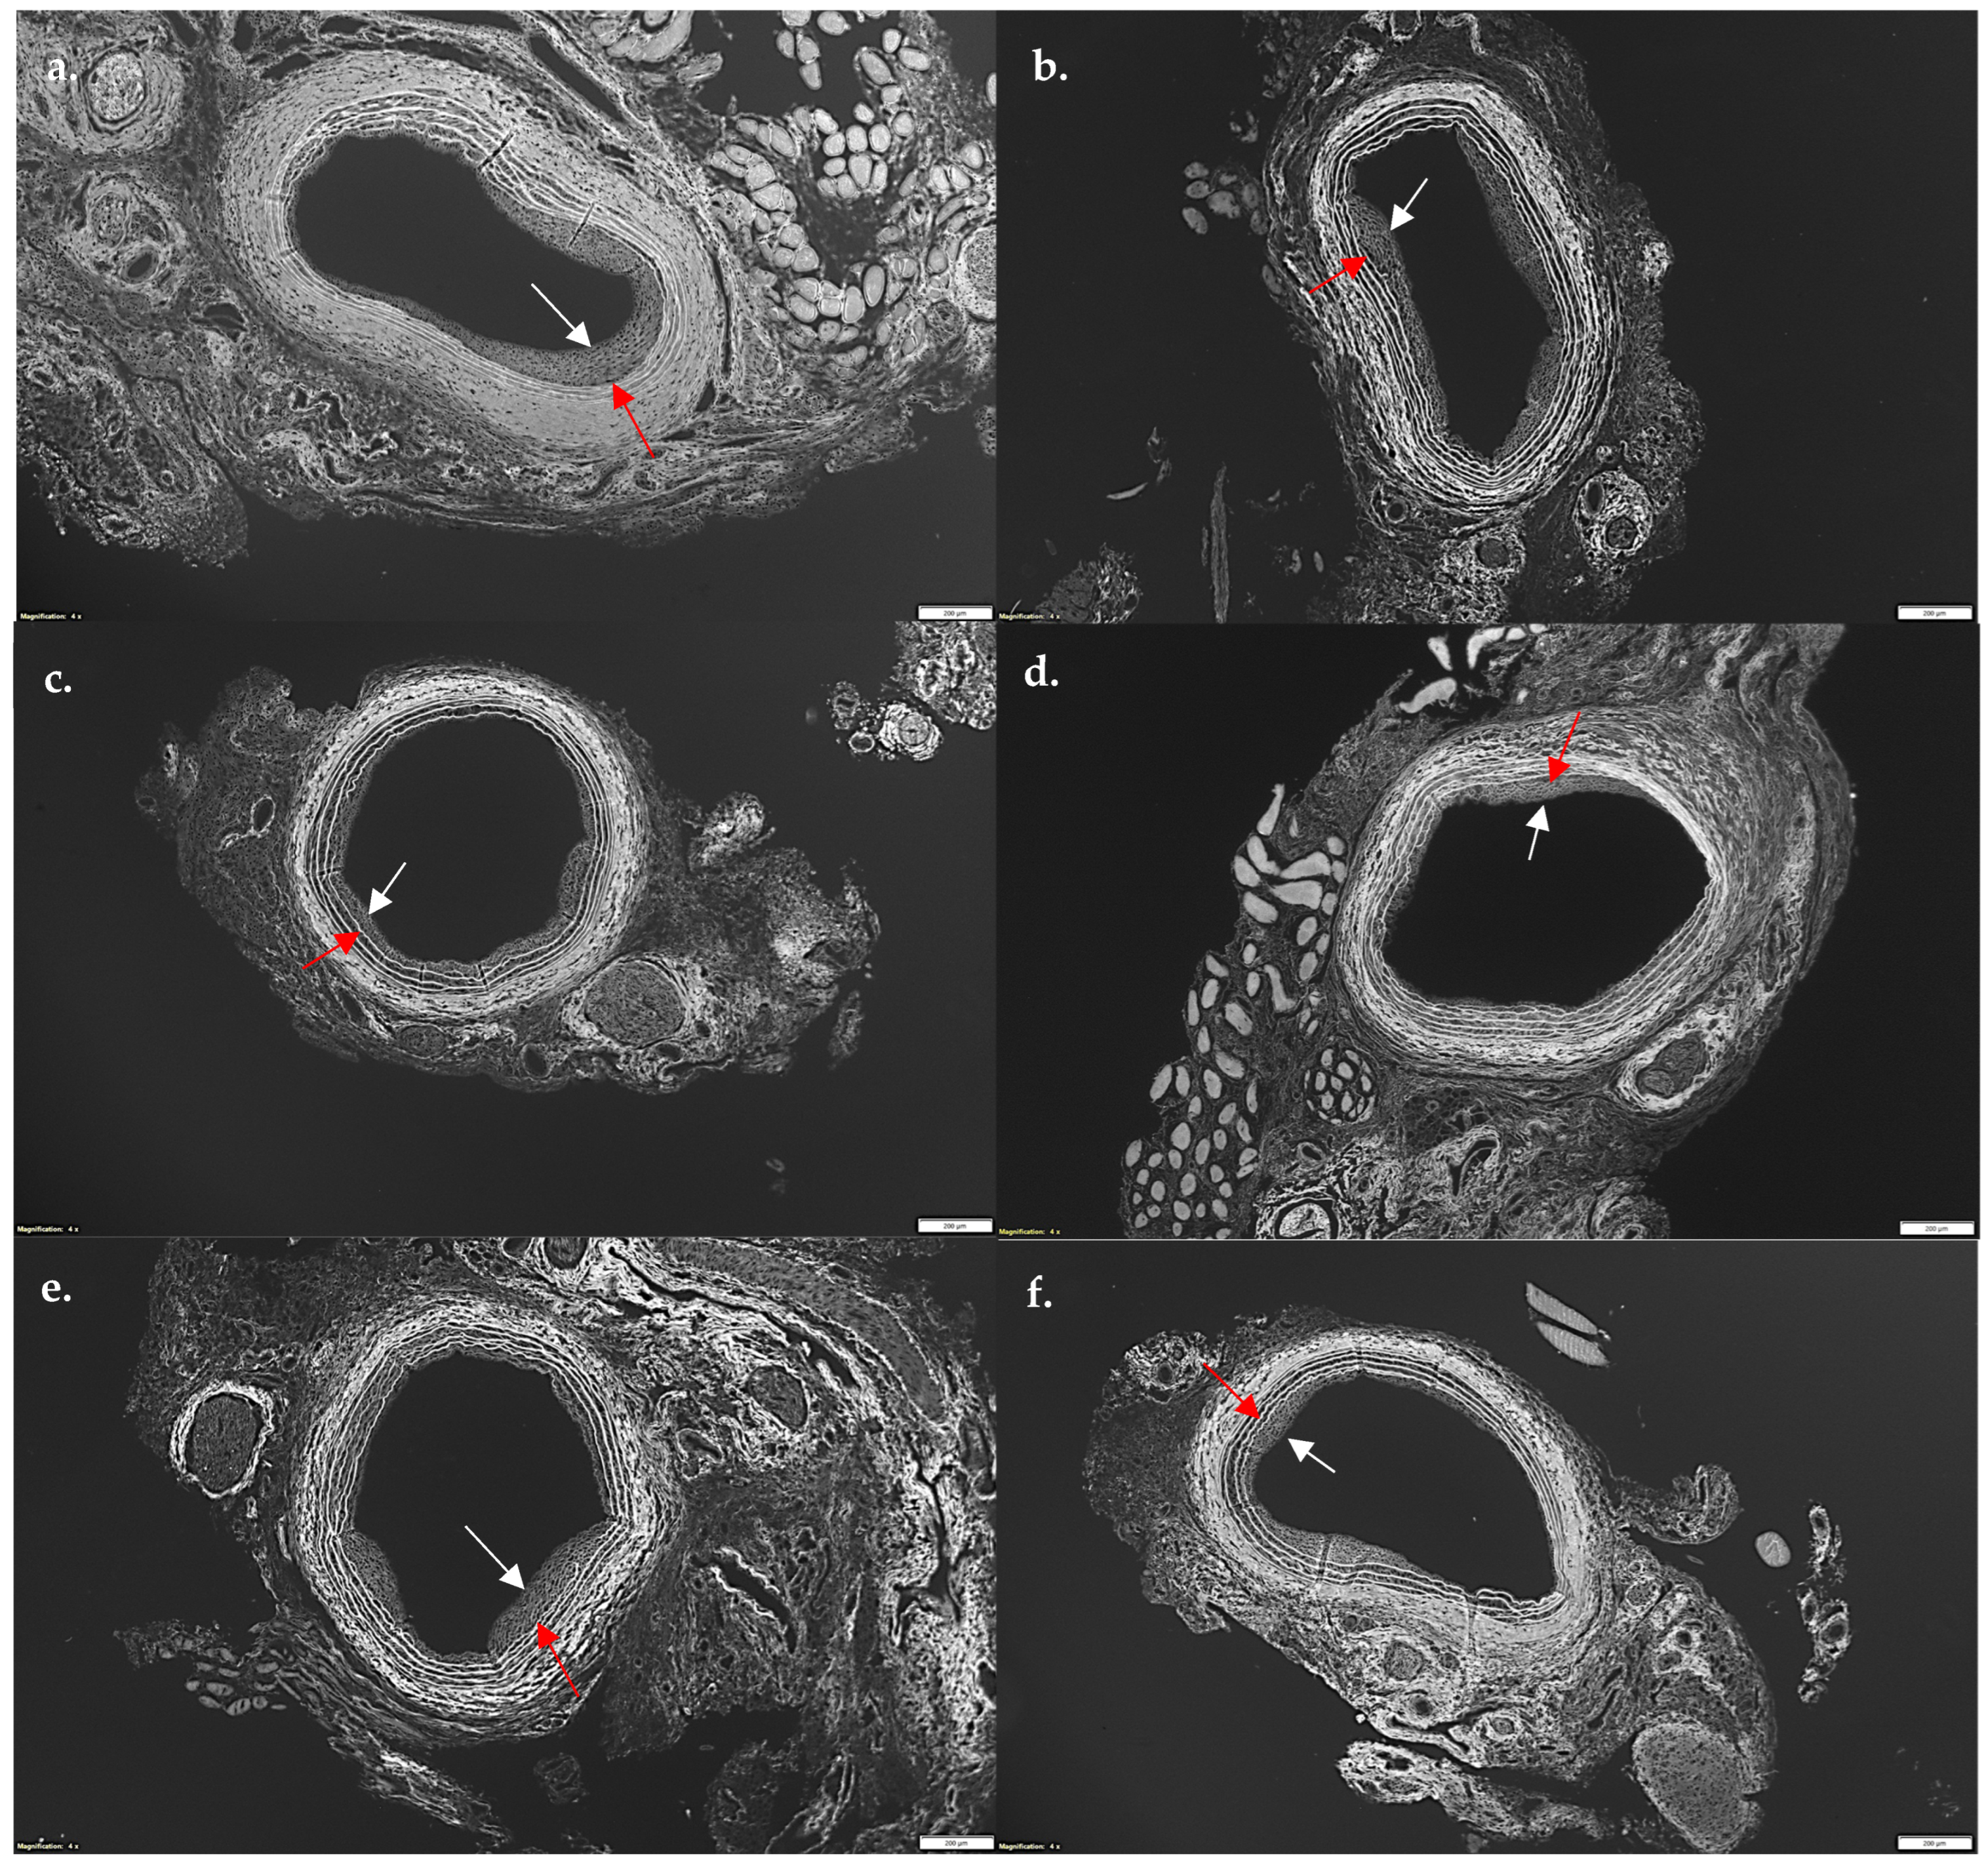

Given SL-cNPs demonstrated increased association to ECs and VSMCs in vitro and demonstrated an effect on gene expression, we assessed their effect on IH in vivo. Localized treatment of either high- or low-dose SL-cNPs was assessed by either administering the cNPs intraluminally as a bolus held in place for 30 min, then removed, or administered periadventitially. Periadventitial administration was injected surrounding the carotid artery following closure of arteriotomy. Mean ± SEM IH ratios were as follows: control animals 0.440 ± 0.04, intraluminal empty-cNPs 0.416 ± 0.05, oral simvastatin 0.35 ± 0.03, high-dose periadventitial SL-cNP 0.35 ± 0.04, low-dose intraluminal SL-cNP 0.377 ± 0.03, high-dose intraluminal 0.41 ± 0.04, and oral + SL-cNPs 0.34 ± 0.03. Representative images of IH are presented in Figure 5a–f (red and white arrows demonstrating area of IH). Only oral simvastatin with the addition of low-dose intraluminal SL-cNPs significantly reduced IH by 23% (0.34 ± 0.03, p < 0.05) compared to the untreated control group. The data are summarized in Figure 6.

Figure 5. Photomicrograph of representative cuts of intimal hyperplasia after balloon injury of carotid arteries. Rats were sacrificed 14 days after balloon injury, and carotid arteries were harvested, perfused, fixed, sectioned, and stained with hematoxylin and eosin. Utilizing autofluorescence, intimal hyperplasia was measured using intimal/medial area ratios. (a) No statin control; (b) empty-cNPs; (c) oral simvastatin; (d) periadventitial SL-cNPs; (e) intraluminal SL-cNPs; (f) intraluminal SL-cNPs and oral simvastatin. Arrows indicate areas of intimal hyperplasia. White bars represent 200 µm.